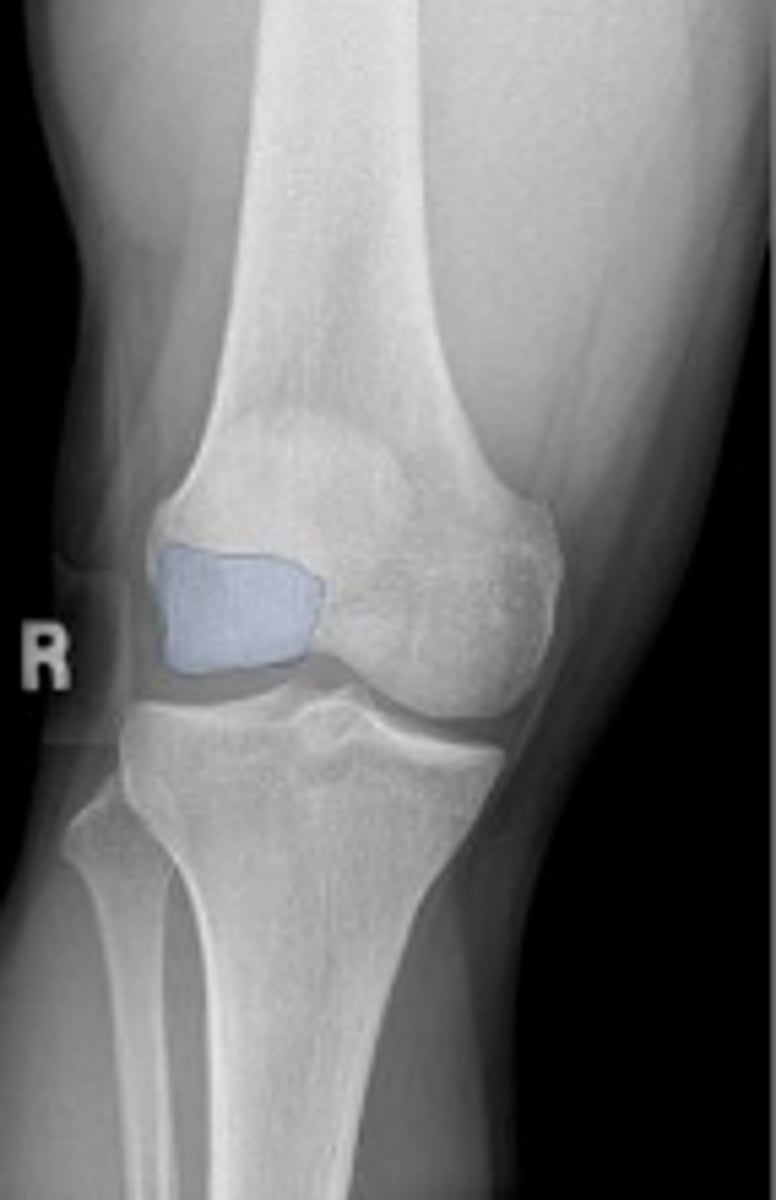

Right internal oblique knee

What is the name of the radiographic view?